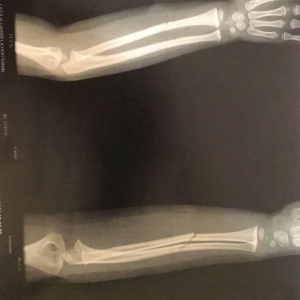

O resultado do exame (imagem acima) apresentou duas fraturas fechadas no braço da criança, que voltou para o hospital Bom Pastor após fazer o Raio-X, e ficou aguardando em um leito a transferência para algum hospital da região a fim de receber atendimento especializado.